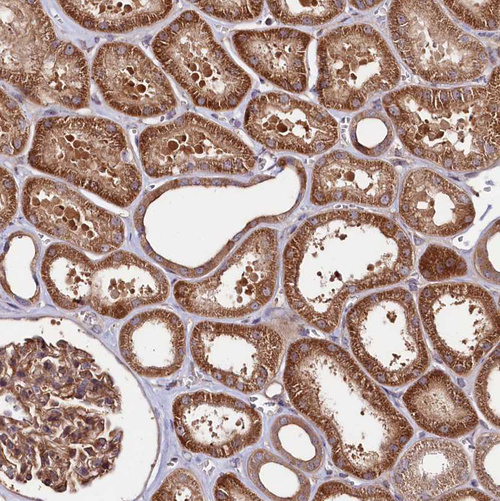

Immunohistochemical staining of human testis shows moderate cytoplasmic positivity in cells in seminiferous ducts.